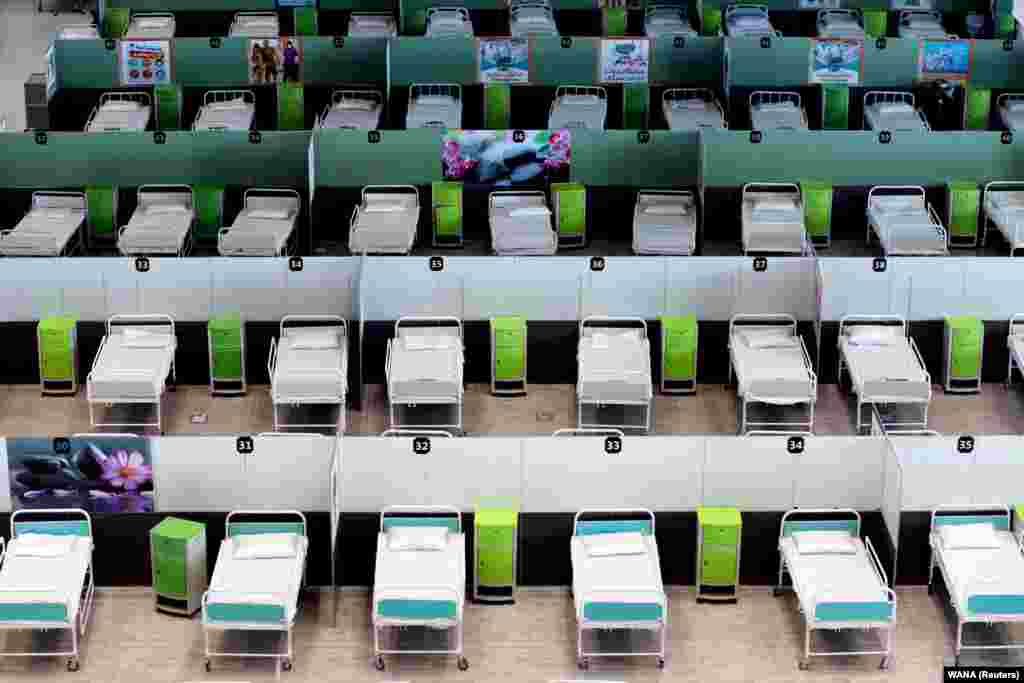

Опыт Китая, Италии, Испании, Франции и США показал, что медицинские учреждения могут «захлебнуться» от тысяч пациентов, нуждающихся в неотложной медицинской помощи. О тех мерах, на которые пришлось пойти правительствам разных стран в ожидании потока больных, рассказываем в фоторепортаже.

Опыт Китая, Италии, Испании, Франции и США показал, что медицинские учреждения могут «захлебнуться» от тысяч пациентов, нуждающихся в неотложной медицинской помощи. О тех мерах, на которые пришлось пойти правительствам разных стран в ожидании потока больных, рассказываем в фоторепортаже.